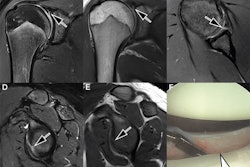

The study included 105 patients who underwent 110 MRI exams. The investigators compared standard shoulder MRI sequences (9 minutes) and accelerated ones (3 minutes) for image quality and diagnostic performance; all patients had both. Standard sequences were reconstructed with conventional techniques, while the accelerated sequences were reconstructed with a conventional technique alone and with a conventional technique plus a deep learning algorithm (AIR Recon DL, GE Healthcare).

Two radiologists evaluated the MRI images for image quality and clarity using a four-point scale (with 1 representing poor and 4 indicating excellent). They also assessed images for artifacts using a four-point scale (with 1 meaning severe artifacts and 4 signifying no artifacts). Scores for each of three imaged planes were added for a total score of 3 to 12 for both image quality and artifacts.

The accelerated MRI shoulder exam sequences were accomplished in 67% less scan time, although they did have poorer image quality and artifacts compared with the standard sequences. But using the deep learning-based reconstruction helped, however.